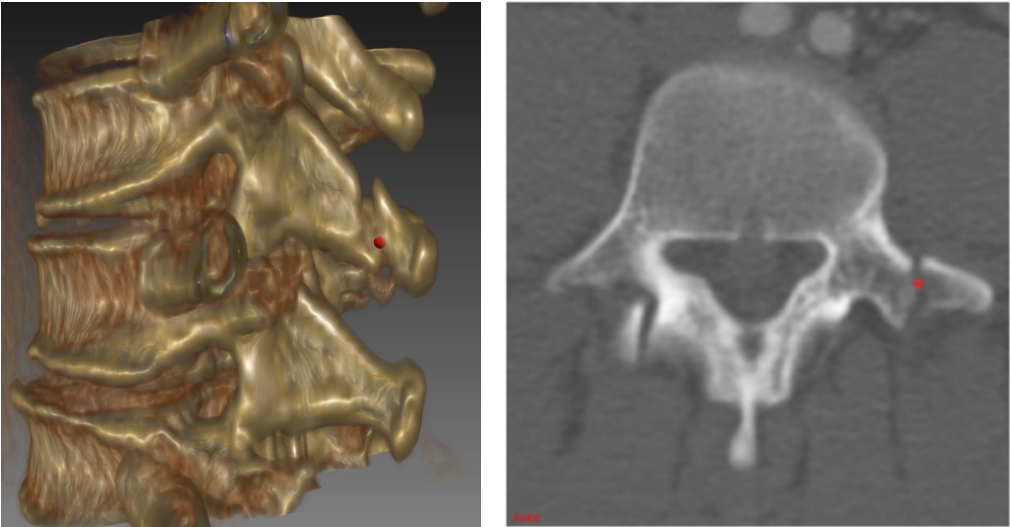

Injuries of the spine and its posterior elements in particular (see Figure 1) are a common occurrence in traumatic patients, with potentially devastating consequences [1]. Spine fractures are detected using volumetric imaging such as computed tomography (CT) in order to access the degree of injury. Spine injuries are a critical concern in blunt trauma, particularly in cases of motor vehicle collision and fall from significant heights. More than 140,000 vertebral fractures occur in the U.S. each year [2]. However, the traditional method of qualitative visual assessment of images for diagnosis could miss fractures, and is time-consuming, potentially causing delays in time-critical situations such as the treatment of spine injuries. Computer-aided detection (CADe) has the potential to expedite the assessment of trauma cases, reduce the chance of misclassification of fractures of the spine, and decrease inter-observer variability. Furthermore, CADe could help assess the stability and chronicity of fractures, as well as facilitate research into optimization of treatment paradigms.

In this work, we apply ConvNets for the automated detection of posterior element fractures of the spine. First, the vertebra bodies of the spine with its posterior elements are segmented in spine CT using multi-atlas label fusion [10, 11]. A set of atlases of the vertebra bodies are registered to the target image with free-form deformation. Then, an edge map of the posterior elements is computed using the Sobel operators

in order to find the horizontal () and vertical () approximations of the image derivative for each CT slice. Here, denotes a convolutional operation. Edge points are located at the maximum of the absolute gradient . The edge maps serve as candidate regions for predicting a set of probabilities for fractures along an image edge using ConvNets. An example of posterior-element segmentation and edge map estimation is shown in Fig. 3.